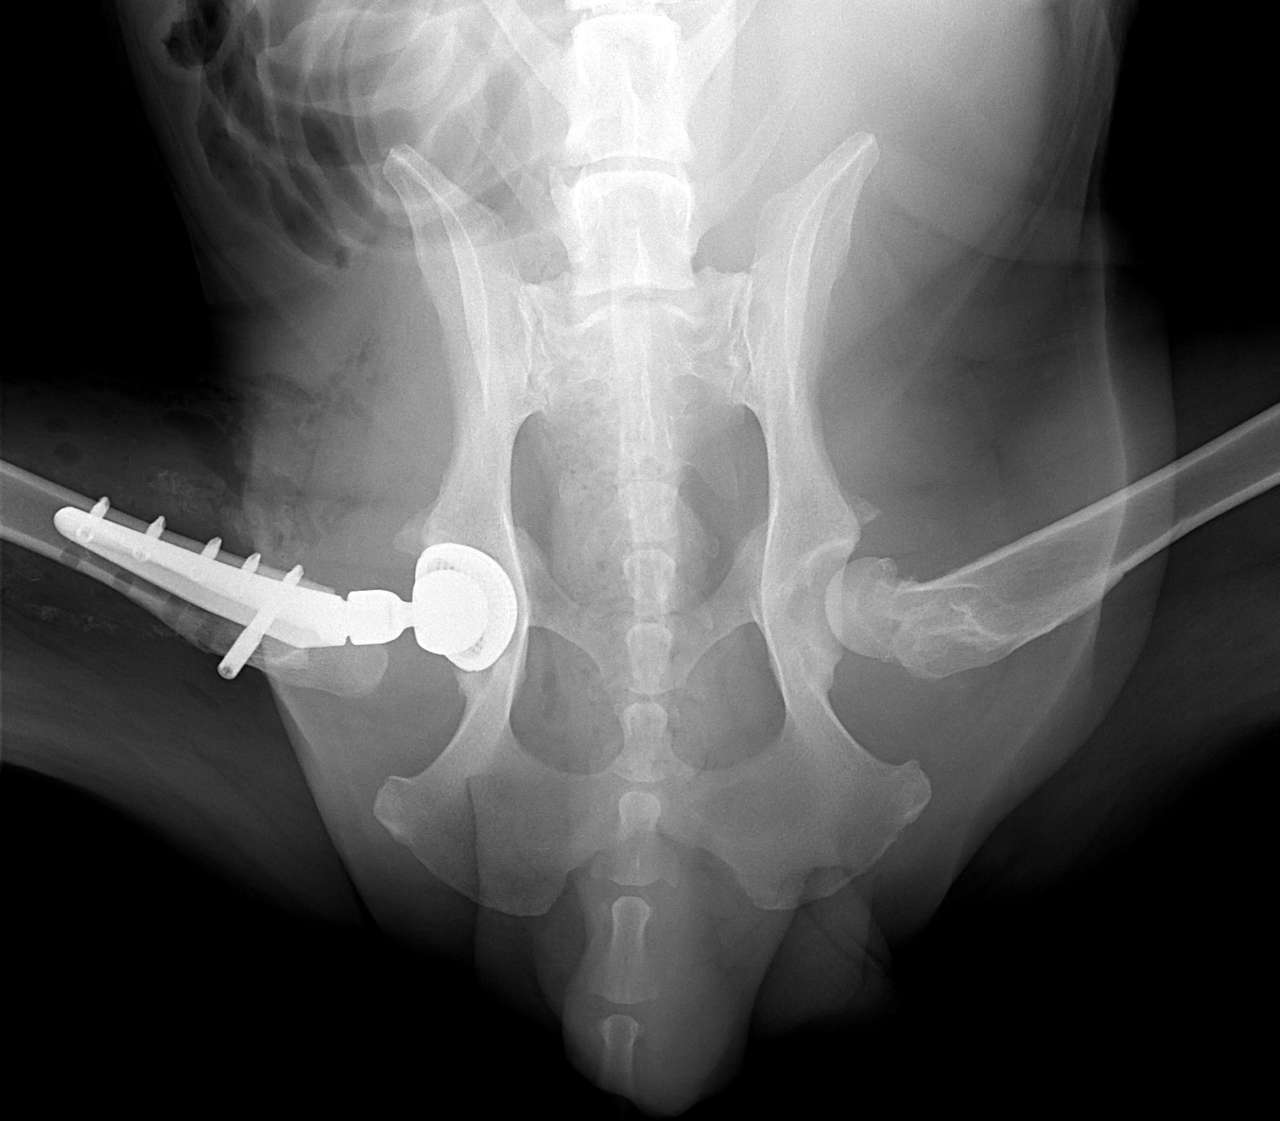

45kgの大型犬が股関節形成不全による痛みがあるとの事。他県より紹介来院されました。KyonのTHRシステム(人工関節)で傷んだ関節を置換しました。関節炎による痛みを感じるのは人も動物も同じです。出来るだけ痛みのない生活を過ごしてもらいたいと思います。インプラントはCup AOL 42° Large STEM 17°、Head19mm、Neck S、29.5 、Cup Anteversion 30°で埋入されています。内科治療に反応のない骨関節炎には人工関節で対応する事も可能です。しばらくは安静が必要です。